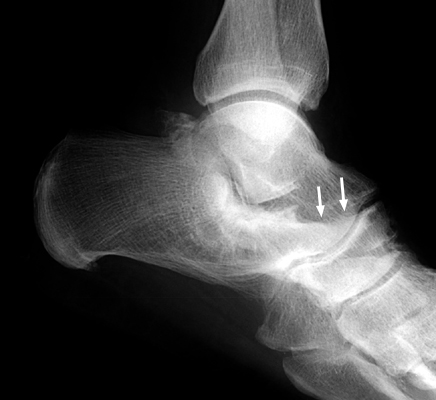

Plain film and CT images of calcaneonavicular coalition. Notice the elongated, tubular like extension of the anterior calcaneus seen on the lateral film; this imagery has been likened to the elongated nose of an anteater. There is abnormal bony fusion of the calcaneus and navicular bones, with the presence of a bony bar extending between these two bones.

- Click on the image for a larger versionALateral foot - Click on the image for a larger versionBCT - Click on the image for a larger versionC